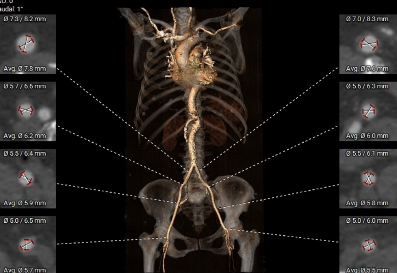

血管三维重建